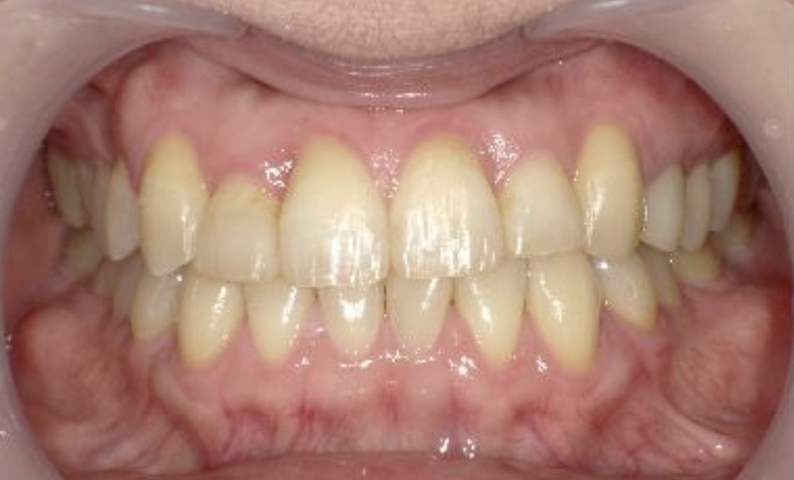

症例_003 下顎だけの部分矯正

治療期間:10ヶ月金額:24万円+税女性前歯のガタガタ下の前歯だけ上顎は補綴治療中

| Before | After |